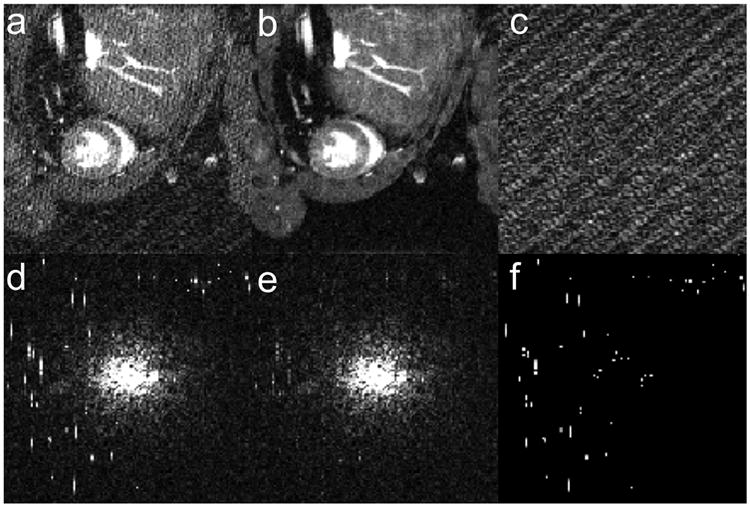

Figure 4.

Demonstration of RPCA despiking applied to a static image. Images (a-c) and k-space data (d-f) for a single frame from the cine data set (frame also displayed in Figure 3). Corrupted data (a, d) is successfully decomposed into low-rank (b, e) and sparse (c, f) components to isolate RF spikes (visible in f) and remove stripe artifact (visible in a).